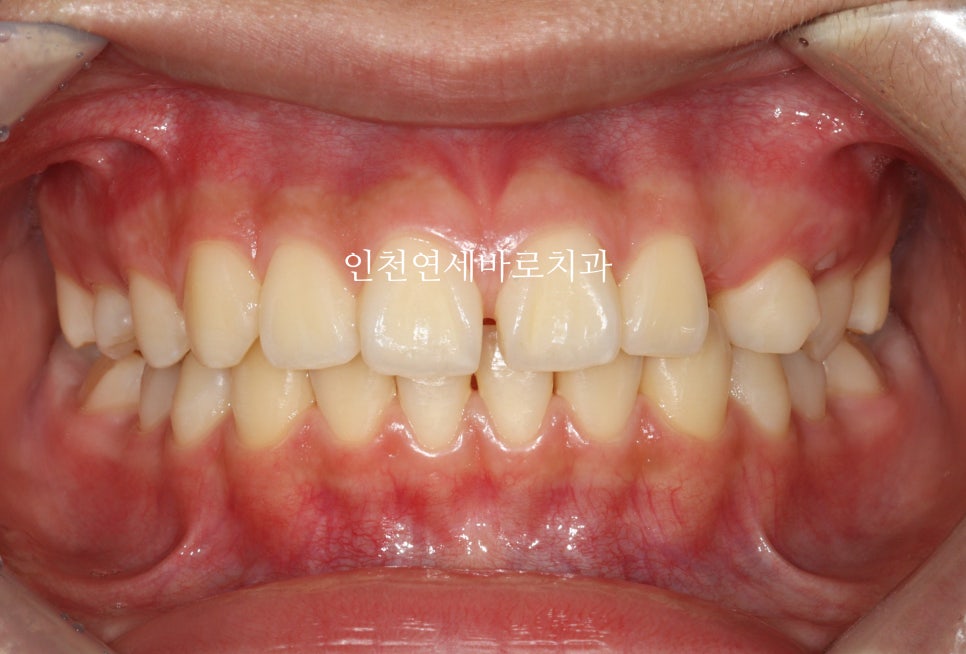

마무리는 장치가 몇개 없이 해결되었습니다.

생각보다 자연맹출도 너무 예쁘게 되었네요

공간을 정확하게 배열해준 덕분이라 생각합니다

총 치료기간은 10개월정도 소요되었습니다.

중심선도 잘 맞고

교합도 양호합니다.

최후방 어금니는 맹출 중 입니다.

화살표 부분의 치아 순서가 일반적인 순서와는 조금 다르지만

기능적, 심미적으로 거의 문제없이 해결했습니다.